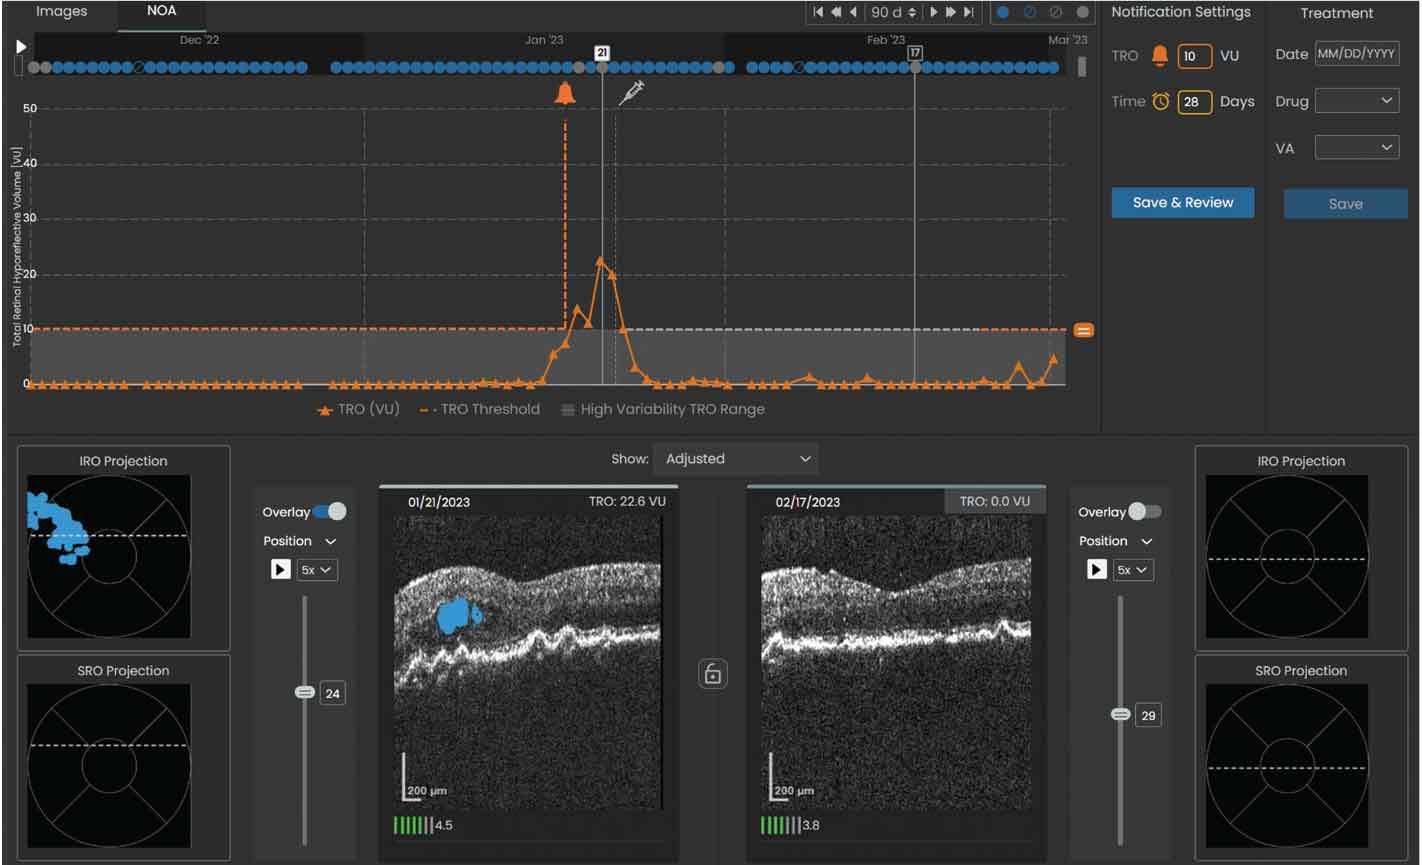

Figure 4. Sample volume trendline showing a notification was sent to the reviewing physician when the total retinal volume crossed the set threshold of 10 µL. The left OCT scan shows the total retinal volume reached a maximum of 22.6 µL within the specified 90-day window on 01/21/23 and was predominantly IRF (denoted by the shaded blue area). |

5. If fluid volume or the time interval exceeds the set threshold (Figures 3 and 4), a notification will prompt review by the retina specialist, and the patient may subsequently be scheduled for an in-office evaluation and injection visit.